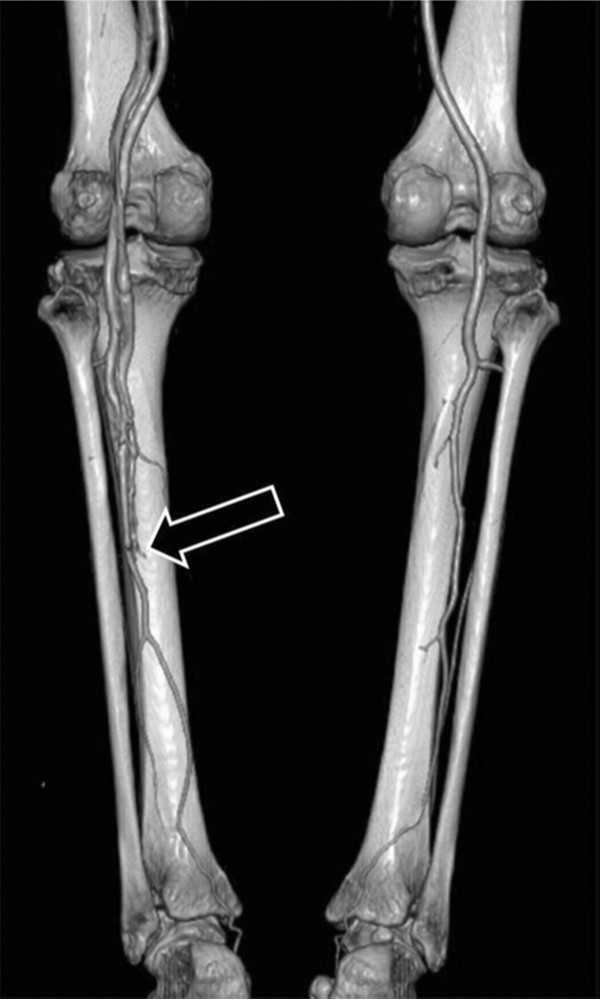

CT 혈관조영술에서 피하 부종은 저명치 않았으나 왼쪽 깊은 정맥들이 동맥기에 조영 증강되는 것이 확인되어 동정맥 샛길을 의심하였다(Fig. 1).

Fig. 1.

Volume rendering image of CT angiography shows early enhancement of deep veins of left lower extremity from middle segment of peroneal vein at arterial phase. Suspected fistular tract is marked with arrow.